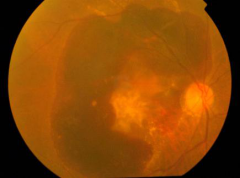

• 玻璃体视网膜

• 糖尿病视网膜病变